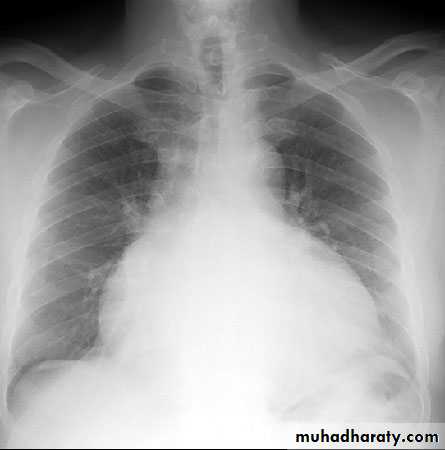

Pericardial Effusion: Investigation

CXR:Globular enlargement of the heart

Rapid enlargement of cardiac shadow over days

The lungs are usually clear